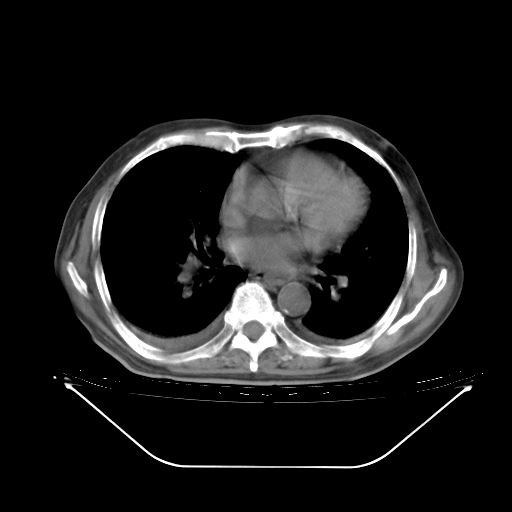

今天复查肺部CT,发现双肺广泛磨玻璃样改变。所以我把3月19日和5月9日相隔50天的肺部CT上传。请大家会诊。

2009年3月19日肺部CT片。

2009年3月19日肺部CT